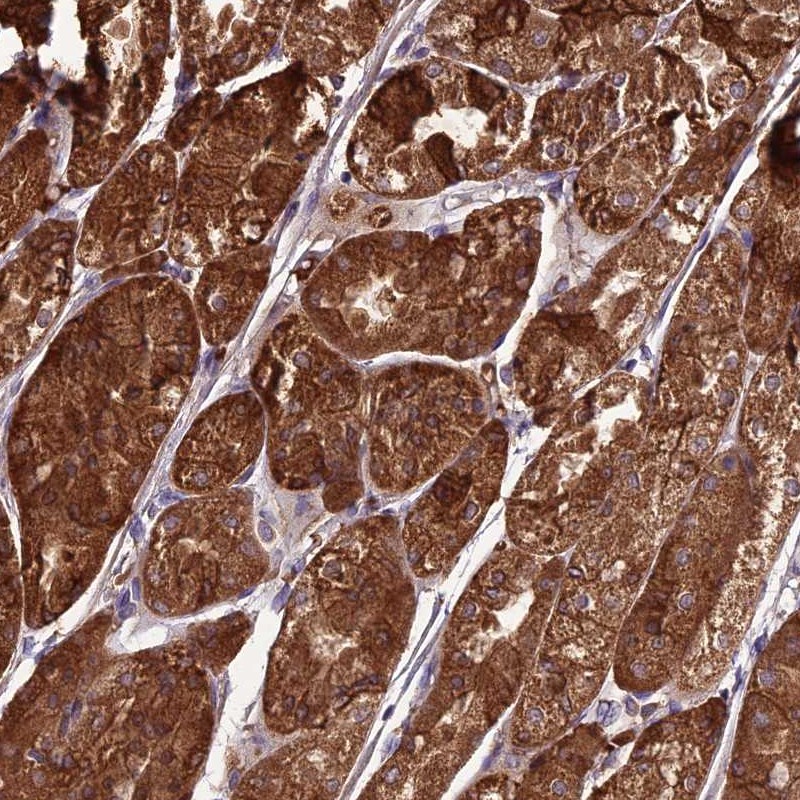

Immunohistochemical staining of human stomach, upper shows strong cytoplasmic positivity in glandular cells.